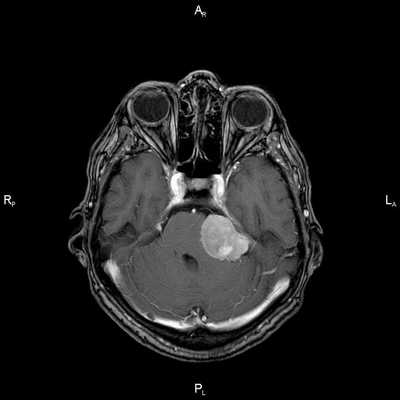

Острый перикардит у мужчины 37 лет. Т1 -взвешенная FSЕ-последовательность с темной кровью в четырехкамерном срезе демонстрирует выраженное утолщение и трудноопределяемый край перикарда (стрелки). Выпот в полость перикарда